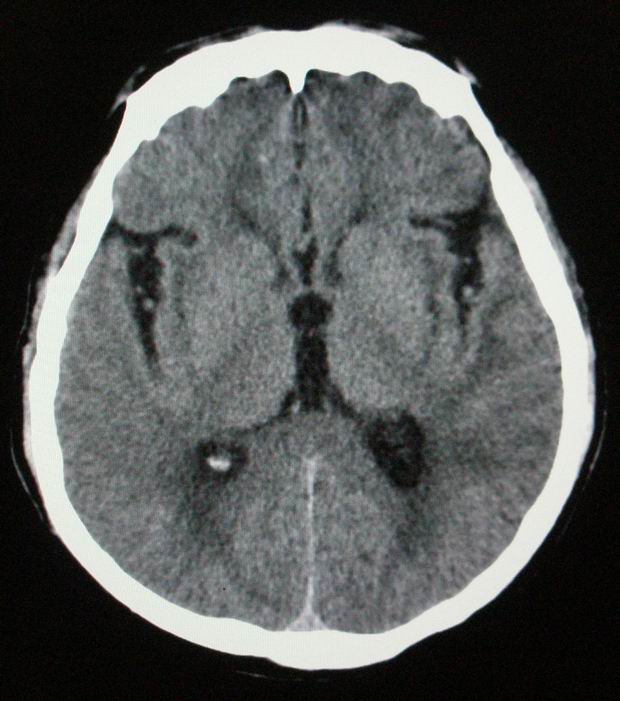

以下是引用随光逐影在2008-4-5 7:46:00的发言:[br]1)考虑为:多发性脑转移瘤。建议:行进一步检查。2)多发性腔隙性脑梗塞。3)脑白质病。4)脑萎缩。

以下是引用zjzjr在2008-4-5 9:00:00的发言:[br]1.双侧颞叶占位性病变,考虑为转移瘤可能性大。[br]2.左侧基底节区陈旧性腔隙性脑梗塞。[br]3.脑白质病。建议mri进一步检查。

以下是引用xuhuihong在2008-4-5 0:59:00的发言:[br]1.双侧颞叶占位性病变,考虑为转移瘤可能性大。[br]2.左侧基底节区陈旧性腔隙性脑梗塞。[br]3.脑白质病。建议mri进一步检查。

以下是引用形影不离在2008-4-4 23:29:00的发言:[br]1.双侧颞叶占位性病变,考虑为转移瘤可能性大。[br]2.左侧基底节区陈旧性腔隙性脑梗塞。[br]3.脑白质病。